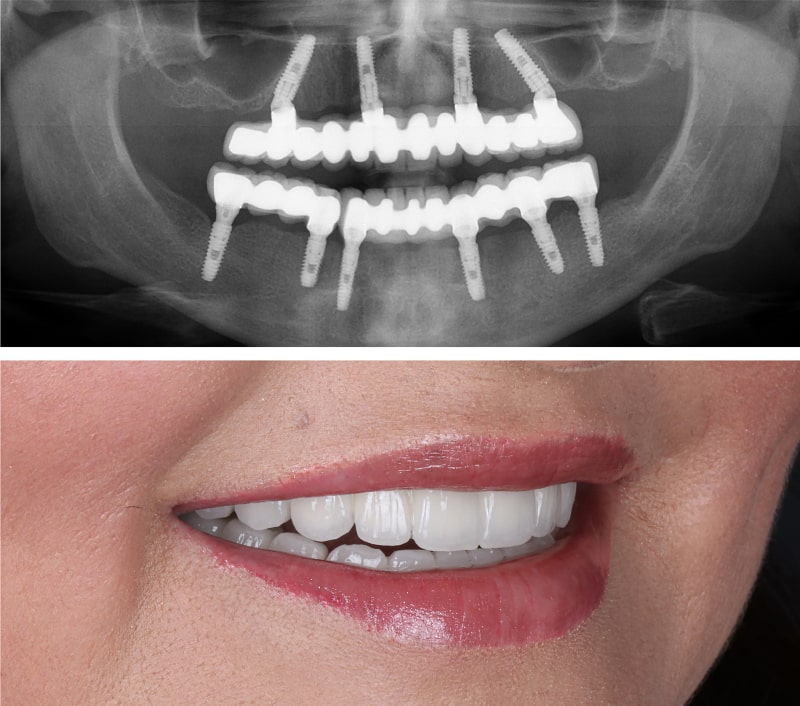

Zahnlosigkeit oder schlechtsitzende Prothesen gehören der Vergangenheit an! In der Siegauenpraxis von Dr. Kai Tolk, BDIZ EDI zertifizierter Implantologe, bieten wir Ihnen mit der innovativen All-on-4™-Methode eine erstklassige Lösung: feste, ästhetische Zähne in nur 48 Stunden – keine Provisorien, sondern hochwertiger, definitiver Zahnersatz! Dank modernster 3D-Planung und minimalinvasiver Techniken erhalten Sie in nur drei Terminen ein stabiles, natürliches Lächeln, das Ihre Lebensqualität spürbar steigert. Verabschieden Sie sich von herausnehmbaren Prothesen und genießen Sie unbeschwerten Komfort beim Essen, Sprechen und Lachen.

Das All-on-4®-Verfahren, entwickelt von Nobel Biocare, ist eine bahnbrechende Lösung für Patienten mit vollständigem Zahnverlust und besticht durch seine Zeit- und Kosteneffizienz. Mit nur vier (oder bei All-on-6® sechs) Implantaten pro Kiefer wird ein kompletter Zahnbogen stabil verankert. Dabei werden zwei Implantate im Frontbereich gerade eingesetzt, während die seitlichen in einem Winkel von 35 bis 45 Grad positioniert werden, um den vorhandenen Kieferknochen optimal zu nutzen. Diese clevere Technik schont empfindliche Strukturen wie Kieferhöhlen im Oberkiefer und den Nervenkanal im Unterkiefer, wodurch in den meisten Fällen kein aufwendiger Knochenaufbau nötig ist.

Der minimal-invasive Eingriff ermöglicht, dass Sie innerhalb von 48 Stunden eine feste, definitive Brücke erhalten – kein Provisorium, sondern ein hochwertiger, passgenauer Zahnersatz, der durch eine Anprobe nach 24 Stunden perfekt sitzt – für ein natürliches Lächeln und spürbare Lebensqualität von Anfang an. All-on-4® steht für Schnelligkeit, Stabilität und Ästhetik ohne Kompromisse!

Die Grundlage für den Erfolg der All-on-4®-Methode in unserer Praxis liegt in der hochmodernen 3D-Diagnostik und digitalen Planung. Mithilfe der digitalen Volumentomographie (DVT) wird der Kieferknochen präzise abgebildet, um die optimale Positionierung der vier Implantate zu gewährleisten. Diese fortschrittliche Technologie ermöglicht eine detaillierte Analyse der Knochenstruktur und schützt sensible Bereiche wie Nervenkanäle oder Kieferhöhlen. Die digitale 3D-Planung sorgt für höchste Präzision beim Setzen der Implantate, minimiert Risiken und macht in vielen Fällen einen aufwendigen Knochenaufbau überflüssig. So entsteht ein perfekt abgestimmter, festsitzender Zahnersatz, der Ihnen in nur einem Tag ein strahlendes Lächeln schenkt!